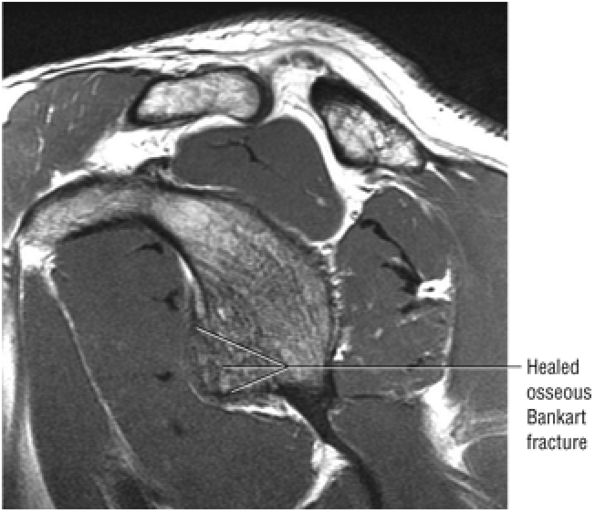

identified. In patients with a history of recurrent dislocations, a sagittal image through the glenoid demonstrates deficiency of the anterior inferior glenoid, manifested as bony Bankart fractures through the anterior inferior glenoid or remodeling and attrition of the anterior inferior glenoid, resulting in an “inverted pear” appearance. Subchondral cystic changes in the glenoid are seen as focal high-signal areas within the glenoid, suggesting overlying chondromalacia.